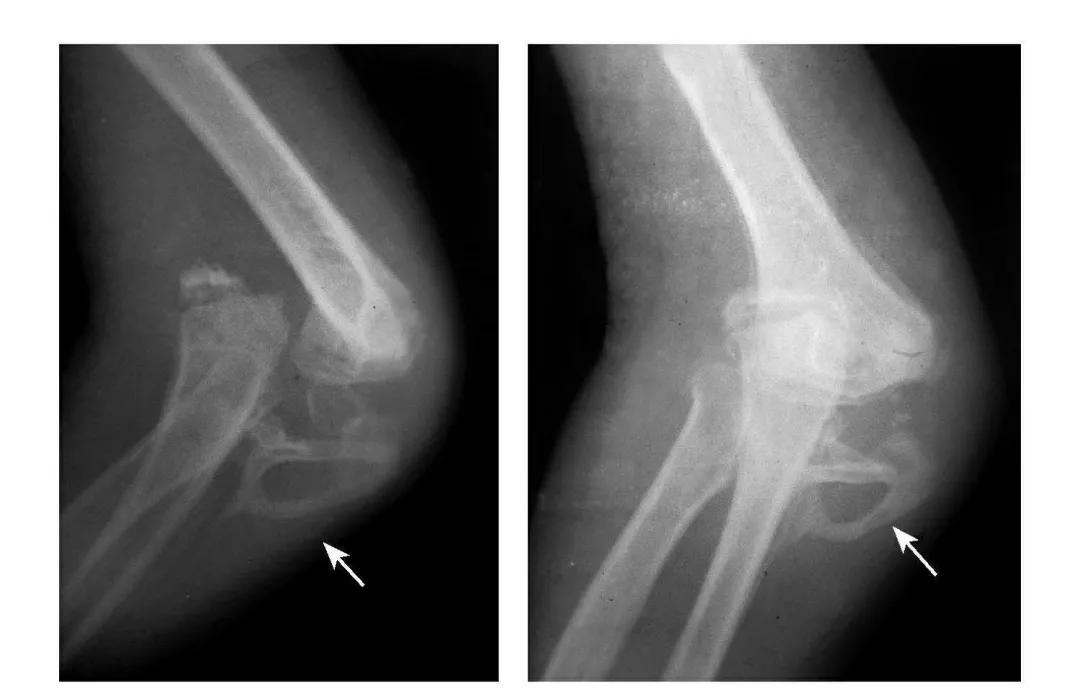

尺骨冠状突骨折

例1:尺骨冠状突撕脱骨折,骨块移向肘前上方。

例2:尺骨冠状突基底骨折,致肘关节不稳,当伸肘位时,肘关节易呈后脱位状。

例3:尺骨冠状突基底部劈裂性骨折,骨块向前外移位并上尺桡关节分离。